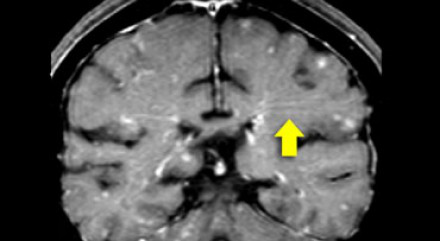

图片十一

上图是该患者冠状位钆增强T1加权成像图像。请仔细观察上图,我们可以看到在基底节中有点状增强病灶,这种病灶特征可见于肉样瘤,也可见于系统性红斑狼疮或其他血管炎性疾病。

该病例中,肉样瘤的典型特征是软脑膜增强(黄色箭头所示),这是由软脑膜发生肉芽肿性炎症造成的。